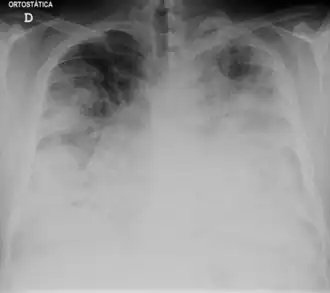

Thoraxfoto tonend ernstige legionellose